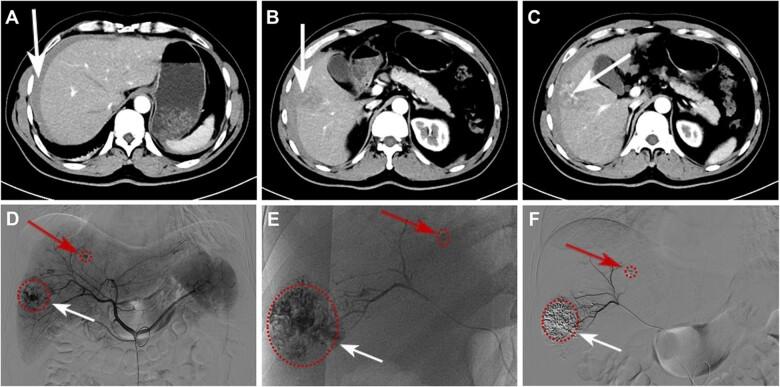

The most common treatment of spontaneous tumor rupture hemorrhage (STRH) is transcatheter arterial embolization (TAE) followed by liver resection, and surgical navigation using near-infrared fluorescence is effective method for detecting hidden lesions and ill-defined tumor boundaries. However, due to the blockage of the tumor-supplying artery after effective TAE treatment, it is difficult to deliver sufficient fluorescent probes to the tumor region. In this study, we report on the successful application of superstable homogeneous intermixed formulation technology (SHIFT) in precise conversion hepatectomy for ruptured hepatocellular carcinoma (HCC). A homogeneous lipiodol-ICG formulation obtained by SHIFT (SHIFT-ICG) was developed for clinical practice for STRH. A ruptured HCC patient received the combined protocol for embolization and fluorescence surgical navigation and exhibited excellent hemostatic effect. Lipiodol and ICG were both effectively deposited in the primary lesion, including a small metastatic lesion. In follow-up laparoscopic hepatectomy, SHIFT-ICG could clearly and precisely image the full tumor regions and boundaries in real time, and even indistinguishable satellite lesions still expressed a remarkable fluorescence intensity. In conclusion, the simple and green SHIFT-ICG formulation can be effectively used in emergency embolization hemostasis and later precise fluorescence navigation hepatectomy in patients with ruptured HCC bleeding and has high clinical application value.

自发性肿瘤破裂出血(STRH)最常见的治疗方法是经导管动脉栓塞术(TAE),随后进行肝切除术,而使用近红外荧光的手术导航是检测隐匿性病变和边界不清的肿瘤边界的有效方法。然而,由于有效的TAE治疗后肿瘤供血动脉被阻断,难以将足够的荧光探针输送到肿瘤区域。在本研究中,我们报告了超稳定均匀混合制剂技术(SHIFT)在破裂肝细胞癌(HCC)精准转化肝切除术中的成功应用。通过SHIFT获得的均匀碘油-吲哚菁绿制剂(SHIFT-ICG)被开发用于STRH的临床实践。一名破裂HCC患者接受了栓塞和荧光手术导航联合方案,显示出优异的止血效果。碘油和吲哚菁绿均有效沉积在原发性病变中,包括一个小转移灶。在后续的腹腔镜肝切除术中,SHIFT-ICG能够实时清晰、精确地成像整个肿瘤区域和边界,甚至难以区分的卫星病灶仍表现出显著的荧光强度。总之,简单且绿色的SHIFT-ICG制剂可有效用于破裂HCC出血患者的急诊栓塞止血及后续精准荧光导航肝切除术,具有较高的临床应用价值。